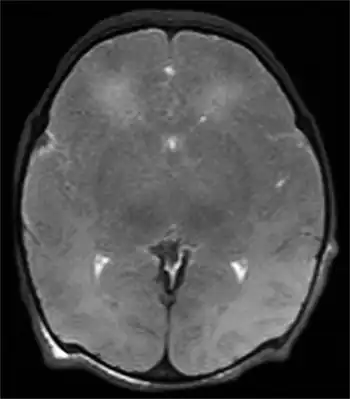

Multiple cerebral ischemic events may lead to subcortical ischemic depression, also known as vascular depression. This condition is most commonly seen in elderly depressed patients. Late onset depression is increasingly seen as a distinct sub-type of depression, and can be detected with an MRI.[11]